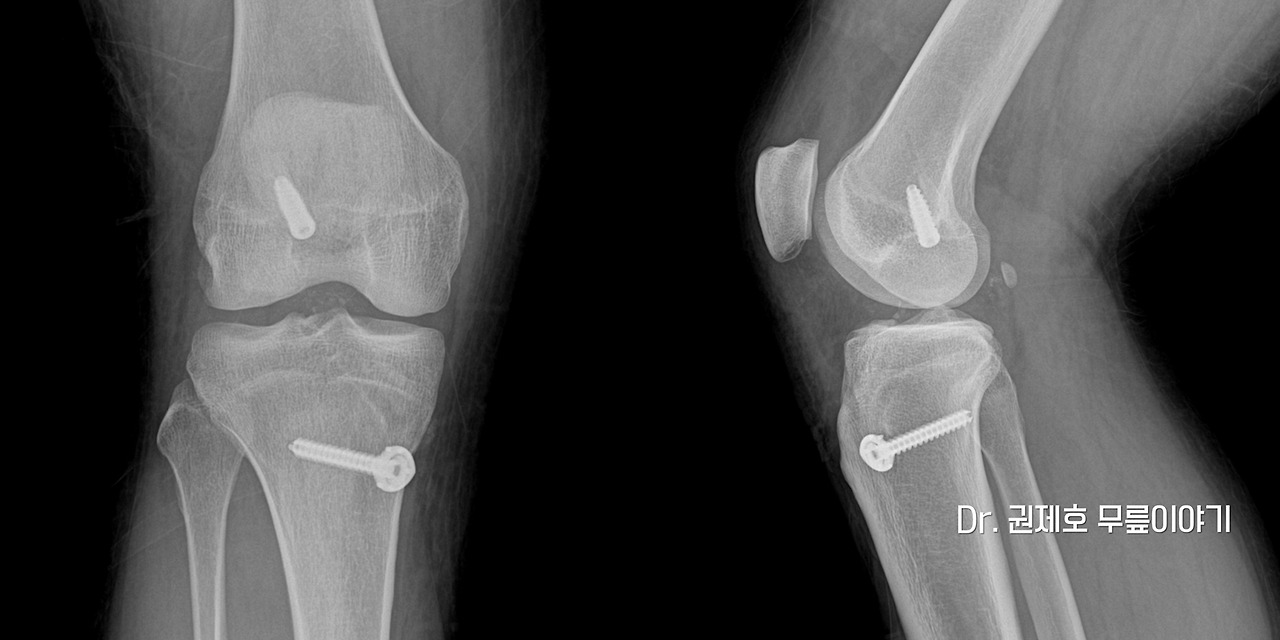

전방십자인대파열 타가건 재건술 (3).jpg 전방십자인대재건술 후 사진

모든 과정이 끝나고, 방사선 사진을 보면 위의 사진처럼 나사못이 두군데 삽입되어 있는 것을 확인할 수 있게 됩니다.